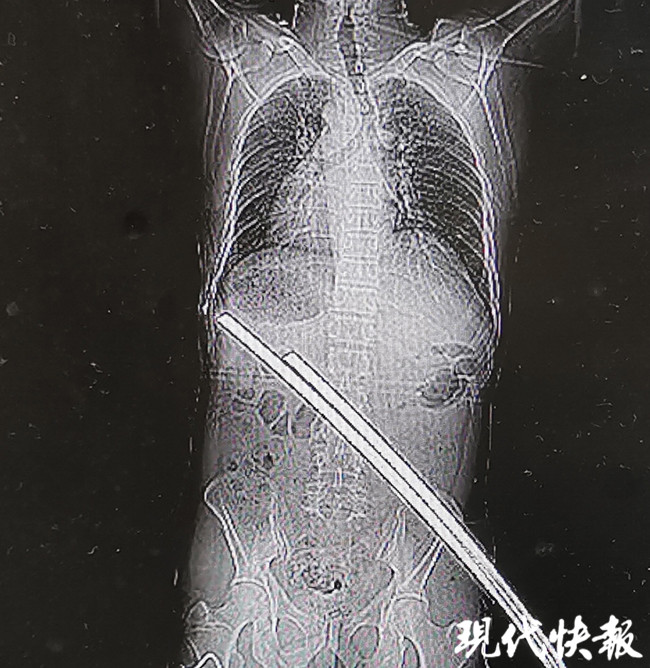

△兩根鋼筋刺穿張師傅腰部

△刺穿張師傅身體的兩根鋼筋

通過CT檢查,醫(yī)生稱鋼筋只是刺穿張師傅的肌肉,萬幸的是并未累及身體重要臟器和血管,除此以外,張師傅肋骨骨折、左肘部皮膚擦傷,無生命危險(xiǎn)。經(jīng)過兩個(gè)小時(shí)的急診手術(shù),鋼筋從張師傅右臀部被拔除,手術(shù)一切順利。